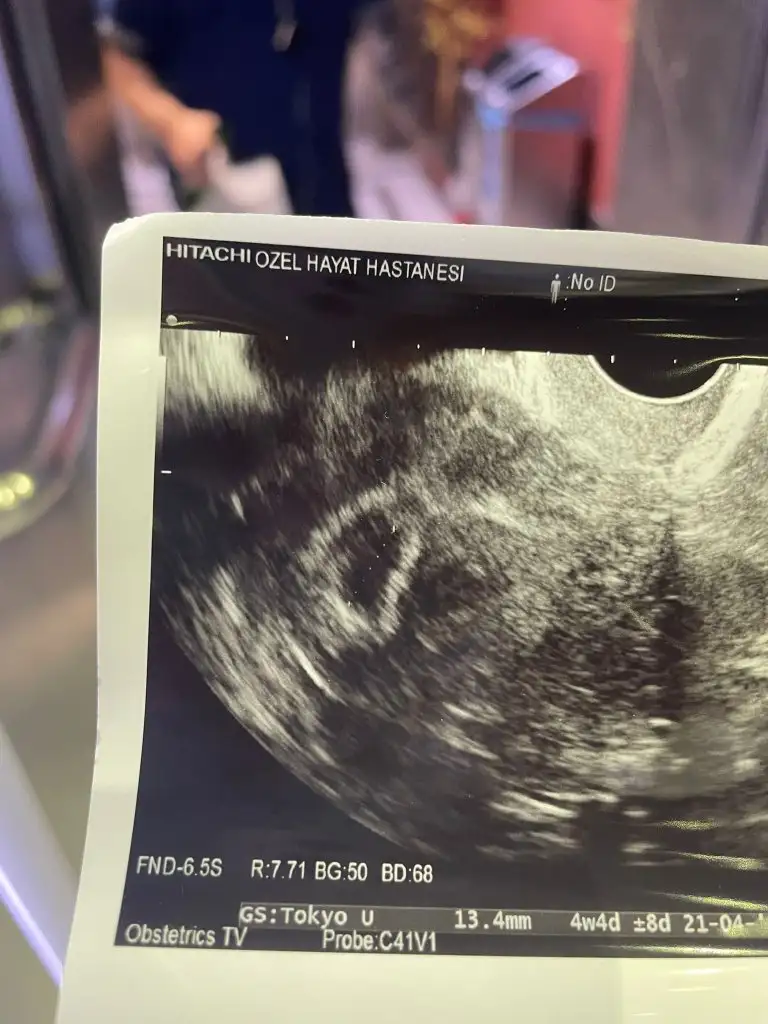

Merhaba arkadaşlar, testim doğru mudur? Gebe miyim? Şu şu belirtiler var acaba olabilir mi? Tarzı sorular çok görüyorum bu yüzden ben de benzer durumdakilere belki yardımcı olur diye yazmak istedim. 38 yaşımdayım Nisan başında embrio oluşmadığı için 10 haftalık gebeliğim kürtaj ile sonlandırıldı, 45 gün adet görmedim. İlk adeti 25 haziranda oldum ve 4 gün sürdü. Ovülasyon testleri bana göre net olmadığından ve beni çok strese soktuğundan(ki artık yumurtlama zamanını sol mememdeki sert ısırılma hissi ve aşırı sıcak basmasından anlıyorum muhtemelen kendimi çok dinlediğim için) iki günde bir ilişki yöntemini denedik. Adetime adetimden 4 gün önce yoğun renksiz akıntıdan şüphelendim ve insan garip bir şekilde hissediyor inanın gidip kan verdim 38.34 çıktı ertesi gün test yaptım aşağıya ekliyorum ne hikmetse normal test daha net sonuç verdi Hamilelik belirtilerim; YERLEŞME KANAMASI YAŞAMADIM gece enseye ani ateş basması sonucu deli gibi terleme, gecede iki kez üst değiştirecek kadar, memelerimde aşırı ötesi hassasiyet(regl zamanı gibi asla değil)hamileliğimi öğrendim ve bir hafta sonra covid oldum ve tahmin edersiniz ki ağlamaktan canım çıktı. Zaten bir kaybım var deli gibi korkuyorum üzerine bir de covid. Neyse ki hepsi geçti bugün çok şükür ki kalp atışını duydum inşallah sağlıkla gelişir. Adetime göre 8 ama ölçüme göre 6 hafta 3 günlük ve 6mm doktor geç döllenme olduğunu söyledi.(aşağıya geçen haftaki kese ve bu haftaki ultrason görünümünü de ekledim örnek olsun diye) Bu arada insülin direncim var, reglim düzensizdi ve tiroid bezim yok belki aynı şeyleri yaşayan arkadaşlar vardır bu başlık bazı sorulara cevap verir. Yüce mevlam dileyen herkesi bir evlada kavuştursun

• 6CD4D195-F7AB-4F00-A6BB-69FD4710F829.webp

9 KB · Görüntüleme: 134

• 08A88810-CCBB-4664-A1B1-A5D6E7C24114.webp

44,6 KB · Görüntüleme: 141

• 31081DE4-453C-40D9-A186-6BA984DBF58E.webp

43,9 KB · Görüntüleme: 131